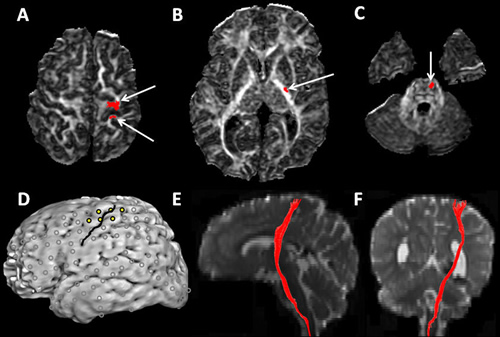

Rationale: The purpose of this study was to determine the cortical origin of corticospinal tract (CST) and its location in the posterior limb of internal capsule (PLIC) using DTI tractography and to compare the CST origin with cortical stimulation data. Methods: This study included 32 children with intractable focal epilepsy (age: 2.2-17.6 yrs; 17 girls), who underwent DTI and functional motor mapping for the primary motor hand area using cortical stimulation. 23 healthy children (age: 2.5-12.4 yrs; 11 girls) also underwent DTI. The CST was delineated by DTI tractography, without presuming precentral gyrus to be the motor cortex: Regions of interest were placed at the anterior portion of the brainstem and at the corona radiata, and the cortical origin as well as its location in the PLIC was determined. In epileptic children, the cortical origin of CST in the affected hemisphere was compared to the location of primary motor hand areas determined by cortical stimulation. Subsequently, the origin of CST and its location in the PLIC in the affected hemisphere of the epileptic children was compared with those in the contralateral hemisphere as well as in controls. Results: In the affected hemisphere of epileptic children, DTI showed that the CST originated from the precentral gyrus in 3 children, from the postcentral gyrus in 4, and from both pre & postcentral gyri in 24 children. Cortical stimulation identified the primary motor hand area in the precentral gyrus in 1 epileptic child, in the postcentral gyrus in 5, and in both pre & postcentral gyri in 23 children. The proportion of overall agreement between cortical stimulation and DTI tractography in localization of motor cortex was 0.86, and positive agreement between these two modalities was found to be 0.92. The pattern of cortical origin of CST was similar between the affected and contralateral hemispheres of epileptic children as well as between epileptic children and controls (Table). In both affected and contralateral hemispheres of the epileptic children and in controls, the CST was located at around two-thirds of the way across from the anterior margin of the PLIC, and occupied about 25% of its dimension. Conclusions: We conclude that the CST frequently originates from both pre and postcentral gyri and is located at the posterior aspect of the PLIC. Furthermore, there is good concordance between DTI tractography and direct cortical stimulation in localization of the primary motor cortex; thus, DTI can be useful in non-invasive localization of CST.